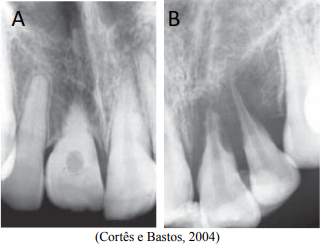

As reabsorções radiculares representam umas das principais complicações pós-traumatismo do processo de reparo das estruturas de sustentação, podendo levar, muitas vezes, à perda do dente. As imagens radiográficas das ilustrações A e B sugerem alterações radiculares, respectivamente, de